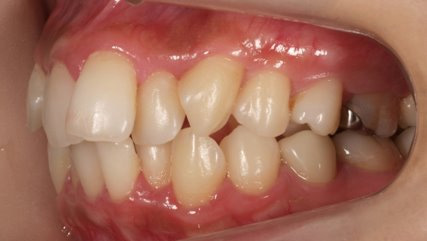

乱ぐい歯、でこぼこがとても酷い状態になります。歯が前後的に重なってしまっている、八重歯になっているなどがこのジャンルに入ります。

顎の大きさと歯の大きさのギャップが大きく、時には歯を抜かないと矯正治療ができない場合もあります。当院では治療期間が長くなるが抜かない治療方針など、一つの治療プランだけでなく、さまざまな可能性の治療方針を説明させて頂くよう心掛けております。こういった考え方はインフォームド・チョイスと言われ近年大切にされている考え方と言われております。

治療前

治療終了前